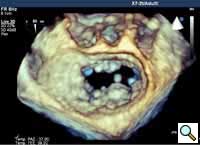

Figure 7

In absence of controlled clinical trial data which are forthcoming from the EVEREST II randomized study, the indications for the MitraClip therapy are currently based on registry experience and will evolve as the technique improves, experience is growing and the data to demonstrate efficacy and safety becomes available. At this time, the best indication for the MitraClip therapy is for symptomatic patients with clinically significant functional or degenerative MR who are at high or increased risk for open heart surgery. From a pure technical standpoint, the procedure so far has only been demonstrated in a subgroup of patients with specific anatomical characteristics which are summarized below and shown in Figure 3. Anatomic suitability is assessed by transesophageal echocardiography, and mitral regurgitation should originate from the central portion of the valve involving the A2-P2 segments, since the device is not ideal to work in the commissures at this time; the mechanism of MR can be either a prolapse/flail or MR due to restricted leaflet motion unrelated to rheumatic disease; the separation between the two leaflets at the site of regurgitation should be limited; severe annular dilatation and/or severe calcification should be absent or is relevant. In case of flail, the flail segment width should be less than 15 mm, and the flail gap less than 10 mm. Figure 4 is a 3D echo image of a patient with posterior leaflet prolapse selected for MitraClip therapy. In case of functional MR, the leaflets should have a minimal residual tissue available for coaptation with the MitraClip device. Figure 5 shows 2D color Doppler jet extension over the coaptation line at TEE short axis transgastric view, while Figure 6 shows the tenting area and the coaptation depth of a patient undergoing MitraClip implant.